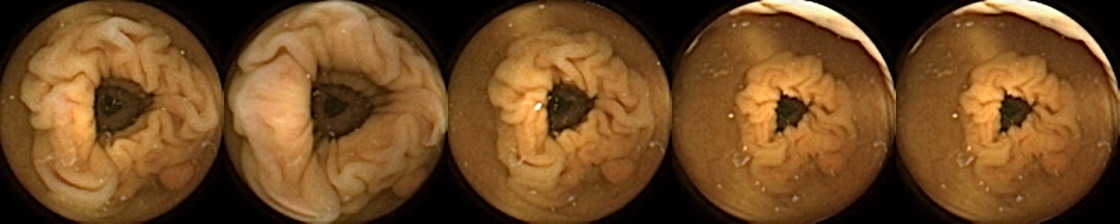

Refer to caption

Figure 1: Positive exemplar images with each row showing five images of a unique polyp, where in each row, the first image corresponds to first partial and fifth image is the last full view of the same polyp. The polyps have been marked in green for each image.

For MIV, we construct both positive and negative exemplar pairs from this multi-patient polyp image dataset. Positive exemplars are constructed based on the five images from a single polyp, with one of the second, third, or fourth image designated as the query and the remaining four images forming the target bag. Images from five example polyps are shown in Figure 1. Negative exemplars are constructed using a more sophisticated strategy: if a patient has multiple polyps, the query image is selected from one of those polyps at random, while target images are sampled from other polyps of the same patient; if a patient has only one polyp, target images are drawn from different patients entirely.